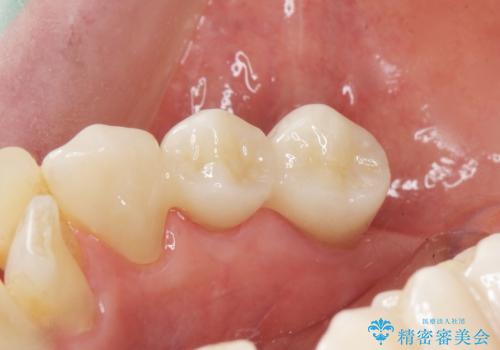

入れ歯も抵抗があるとのことから、相談を重ね、今の状態では保存不可能な下の前歯(左下2)を抜去し、ブリッジや連結補綴により動揺を抑えることにしました。

気にされていた前歯と奥歯の動揺がなくなったことと自然な仕上がりに喜んで頂けました。

クラウンの種類:オールセラミッククラウン スタンダード